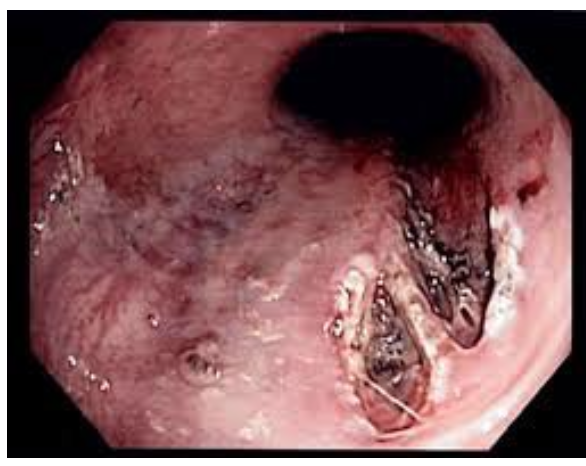

portal hypertensive gastropathy